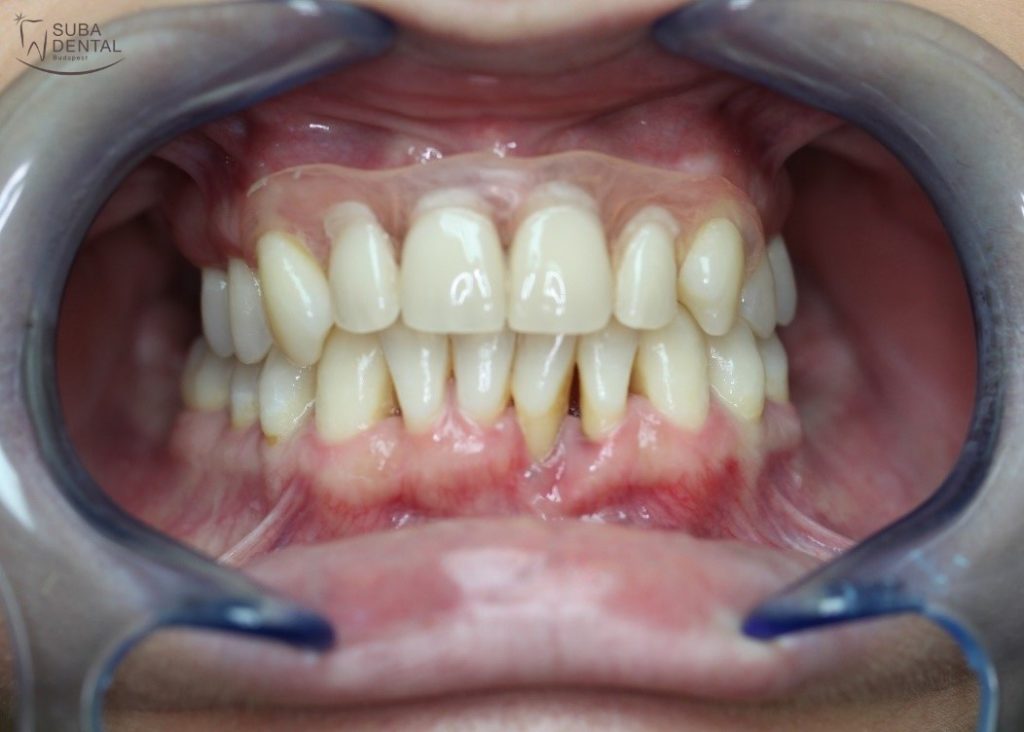

A kész felső fémkerámia körhíd szájban

Előtte

Utána